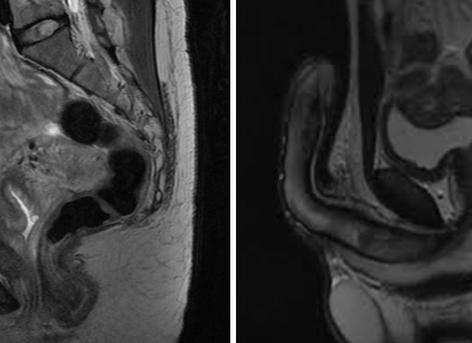

Какую патологию и как позволяет выявить МРТ малого таза у женщин

У женщин репродуктивные органы находятся внутри малого таза и недоступны визуальному осмотру и пальпации. Диагностика заболеваний мочеполовой системы, как правило, требуют инструментальных методов исследования, немаловажную роль среди них занимает МРТ органов малого таза.

В малом тазу у женщины находятся органы разных систем организма:

• мочевыделительной: мочевой пузырь и мочеиспускательный канал;

• репродуктивной: матка, ее придатки (яичники и маточные трубы), влагалище;

• пищеварительной: прямая кишка.

Органы находятся в тесном соприкосновении друг с другом, имея общую иннервацию, кровоснабжение и лимфатическую систему. Пространство между ними заполнено жировой прослойкой.

Часто симптомы патологии разных систем трудно дифференцировать между собой, иногда патология распространяется сразу на несколько органов. Разобраться в сложных диагностических ситуациях помогает МРТ органов малого таза.

• Онкологические процессы. Позволяет установить точные размеры опухоли, ее положение в исходном органе (внутри, в стенке, снаружи), прорастание в другие органы и жировую клетчатку, метастазирование в лимфатические узлы. На основании этого метода будет вырабатываться основная тактика лечения выявленной патологии.

• Эндометриоз. Заболевание сопровождается разрастанием слизистого слоя матки (эндометрия) за пределы нормального расположения: в мышечный слой матки, яичники, кишечник. Это заболевание сопровождается развитием кровоизлияний в пораженные органы и развитием воспалительных процессов в них. Определить стадию эндометриоза, а также масштаб распространения процесса.

• Кисты яичников. Определить размер кисты яичника, а также дифференцировать ее от созревшего фолликула или полостной формы онкологического процесса.